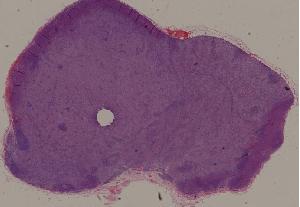

36. Lymphoma